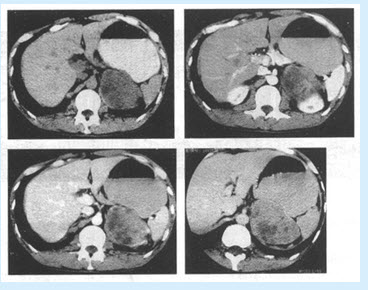

(单选题)双肾CT增强扫描图像如下,可诊断为()

A:肾癌

B:肾盂癌

C:肾囊肿

D:肾错构瘤

E:肾母细胞瘤

(单选题)下列关于肾癌的说法,错误的是()

A:病灶可合并出血、钙化

B:是乏血供肿瘤

C:发病年龄多在40岁以上,男性多于女性

D:典型增强表现为"快进快出"

E:肾实质内肿块